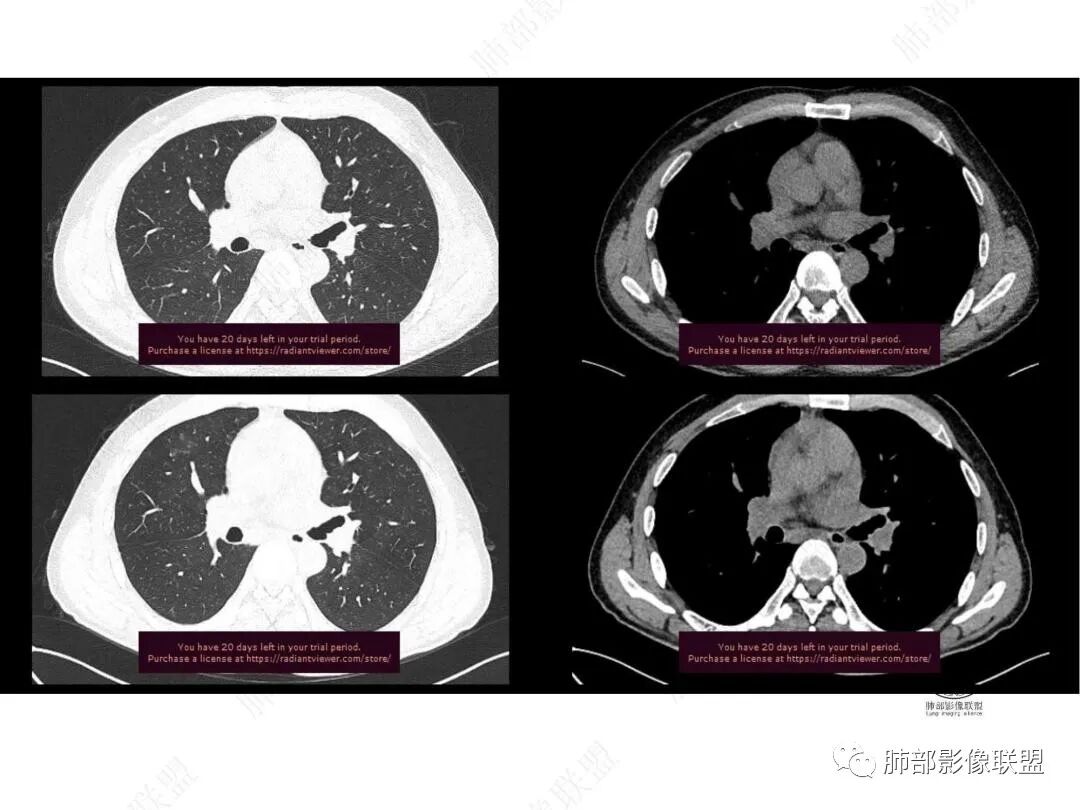

平扫图像

增强图像

1年2个月图像变化:

右上叶前段胸膜下新发病灶;纵隔淋巴结较前增大

1.中年男性,临床发热,症状较轻,中长病程,炎性指标轻度增高。

2.右肺上叶纵隔旁新发实性密度病灶,密度均匀,轻度强化,未见空洞、液化坏死及钙化,血管穿行自如,支气管进入后狭窄截止。灶周磨玻璃影边界不清,病灶未见明显分叶毛刺,平直、轻度收缩、周围偶见结节影,但未见树芽征。注意纵隔胸膜侵入或突入比较明确。纵隔淋巴结轻度增大。